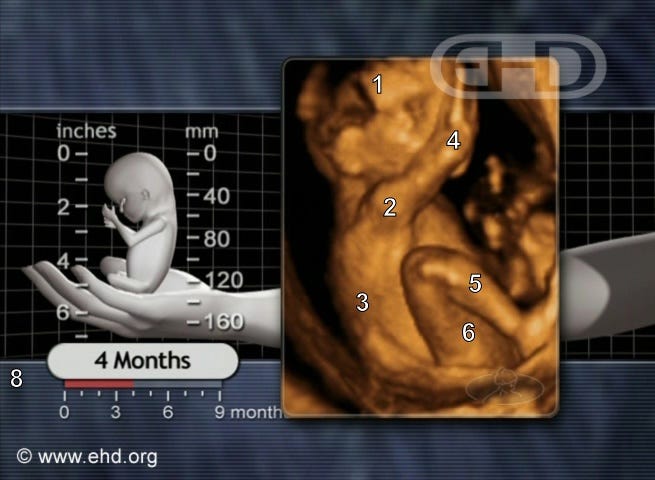

Here is an ultrasound of a 16-week-old preborn baby. This would be the 18th week of pregnancy, within the time frame.

(The discrepancy is caused by the fact that pregnancy is counted from the date of the first day of the last menstrual period, but conception occurs two weeks after the period when ovulation occurs.)